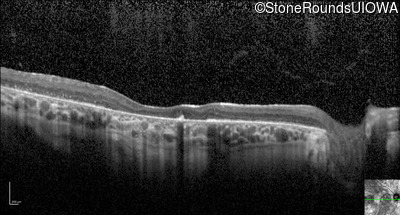

Optical Coherence Tomography - Right - 20/200 +2

Exemplar / OCT Stack